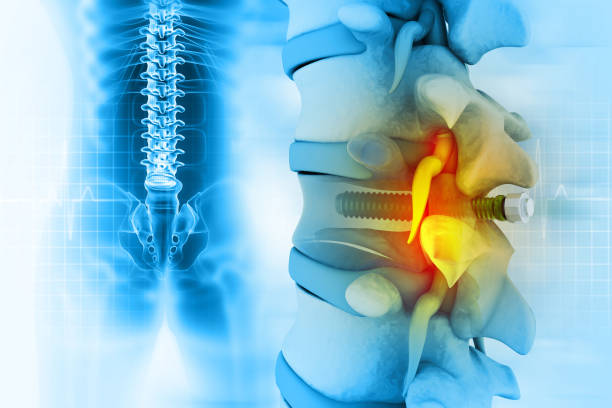

척추관협착증은 척추의 퇴행성 변화로 인해 발생합니다.

이 질환은 척추 내의 신경관이 좁아지면서 다양한 증상을 일으킵니다.

척추관협착증 치료방법 (신경 주사와 시술)

- 신경 주사는 스테로이드를 포함할 수 있으며, 적절한 사용 시 큰 부작용 없이 효과적입니다.

- 시술은 수술을 대체하는 것이 아니며, 신경 주위에 약물을 효과적으로 전달하는 방법입니다.